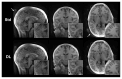

Magnetic Resonance Imaging (MRI) scanners produce loud acoustic noise originating from vibrational Lorentz forces induced by rapidly changing currents in the magnetic field gradient coils. Using zero echo time (ZTE) MRI pulse sequences, gradient switching can be reduced to a minimum, which enables near silent operation.Besides silent MRI, ZTE offers further interesting characteristics, including a nominal echo time of TE = 0 (thus capturing short-lived signals from MR tissues which are otherwise MR-invisible), 3D radial sampling (providing motion robustness), and ultra-short repetition times (providing fast and efficient scanning).In this work we describe the main concepts behind ZTE imaging with a focus on conceptual understanding of the imaging sequences, relevant acquisition parameters, commonly observed image artefacts, and image contrasts. We will further describe a range of methods for anatomical and functional neuroimaging, together with recommendations for successful implementation.